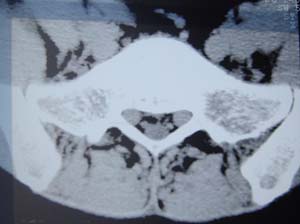

本人的片子,腰腿痛多年,时轻时重。请各位老师发表高见!

1.l4~5间盘膨出伴突出(中央型)

2.l5-s1后纵韧带钙化.